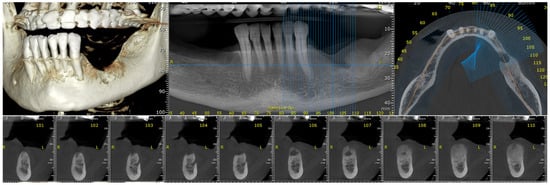

2.1. Examination

2.2. First Surgical Intervention